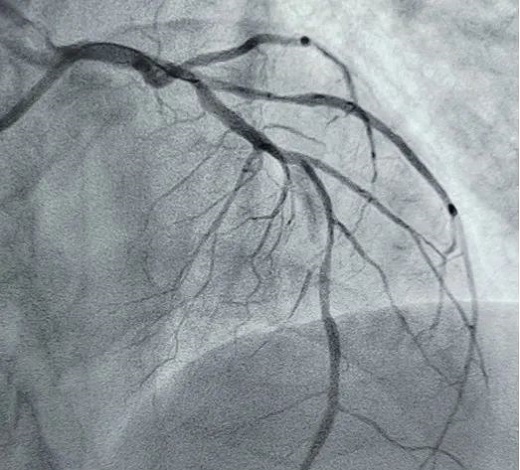

立即啟動綠色通道,急診冠脈造影,結果顯示前降支近段閉塞,血栓負荷較重,先后給予血栓抽吸及球囊擴張,血流恢復正常。李桂武主任和劉興剛主任發(fā)現(xiàn)患者近段狹窄達70%,且中遠段嚴重狹窄伴鈣化,此時不適合同期植入支架,如植入支架可能會引發(fā)血管破裂危及生命。當務之急是快速評估出患者是否可以下手術臺,選擇擇期進行處理,但僅根據造影結果又很難做出判斷,李桂武主任和劉興剛主任快速討論研究最后一致決定,給予患者行冠脈OCT檢查,明確病變性質。

經OCT檢查結果顯示:前降支中段鈣化,內膜光滑,最小管腔面積僅為1.19 mm2。近段斑塊破裂,可見血栓影,最小面積為2.63mm2??蛇x擇先進行抗栓治療,擇期處理冠脈病變。這讓張先生懸著的一顆心終于放下來。